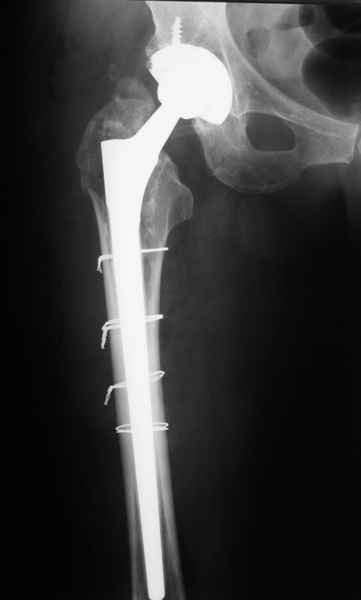

Произведено закрытое удлинение ножки эндопротеза с помощью ретроградного интрамедуллярного стержня. Продолжительность операции 3 часа. Два из них закрытое восстановление длины бедра диистрактором

таз-бедро.

новые снимки

Пациента удалось осмотреть недавно. Достигнутый результат сохраняется. Перелом бедра сросся. Конечность опорная и безболезненная, ходит без трости. Ножка, похоже, реинтегрировалась, как и надеялись. Снимки и фото в приложении. Комментарии приветствуются.

Надо ли что-то делать дальше, как полагаете? Убрать винты? Убрать "удлинитель ножки"? Или оставить все, как есть? Спасибо заранее.